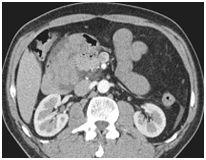

Other abdominal symptoms were found: abdominal pain (n=11), nausea (n=8), vomiting (n=9). The interval between the beginning of symptoms and hospitalization ranged from 24 to 72hours (mean: 48hours). The physical exam revealed abdominal distention in 6patients (54, 55%), abdominal tenderness in 2patients (18, 2%), and peritonitis in tow patients (18, 2%). Abdominal X-ray showed air fluid levels in nine patients (81, 82%). Ultra sonography examination showed peritoneal fluid in five patients. CT scan was done in seven patients on emergency. It suggested non specific internal herniation in five patients. In the other two patients, it suggested a specific internal herniation: a right parduodenal hernia in tow cases (Figure 1).

Figure 1 Abdominal CT scan showing right paraduodenal hernia with twisted bowel loops through it.